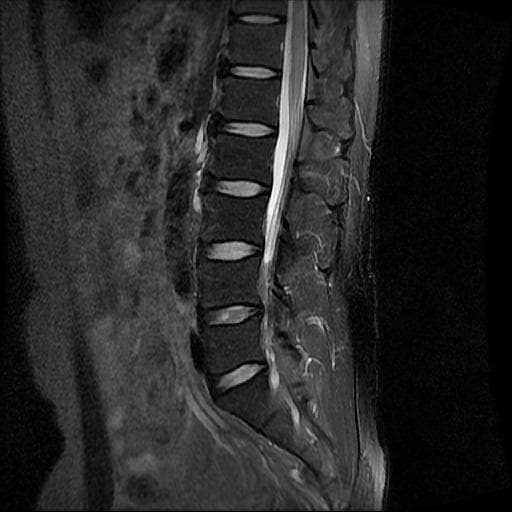

허리 MRI 디스크 상태 분석 부탁드립니다

검진 차 MRI찍었는데 분석 부탁드립니다.

건협에서는 관리해야 된다는데 디스크 협착이나 팽윤 등이 있는 상태인지 궁금합니다.

우선 현재로썬 사진만으론 판단을 하기에 제한이 되지만 사진상 디스크 상태는 심해보이지 않습니다.

요추부위의 하부 에서 약간의 팽윤이나 돌출로 의심해볼수 있는 정도이지만, 정확한 상태는 관련 전문의에게 진료시 문의를 하시는 것을 추천드립니다.